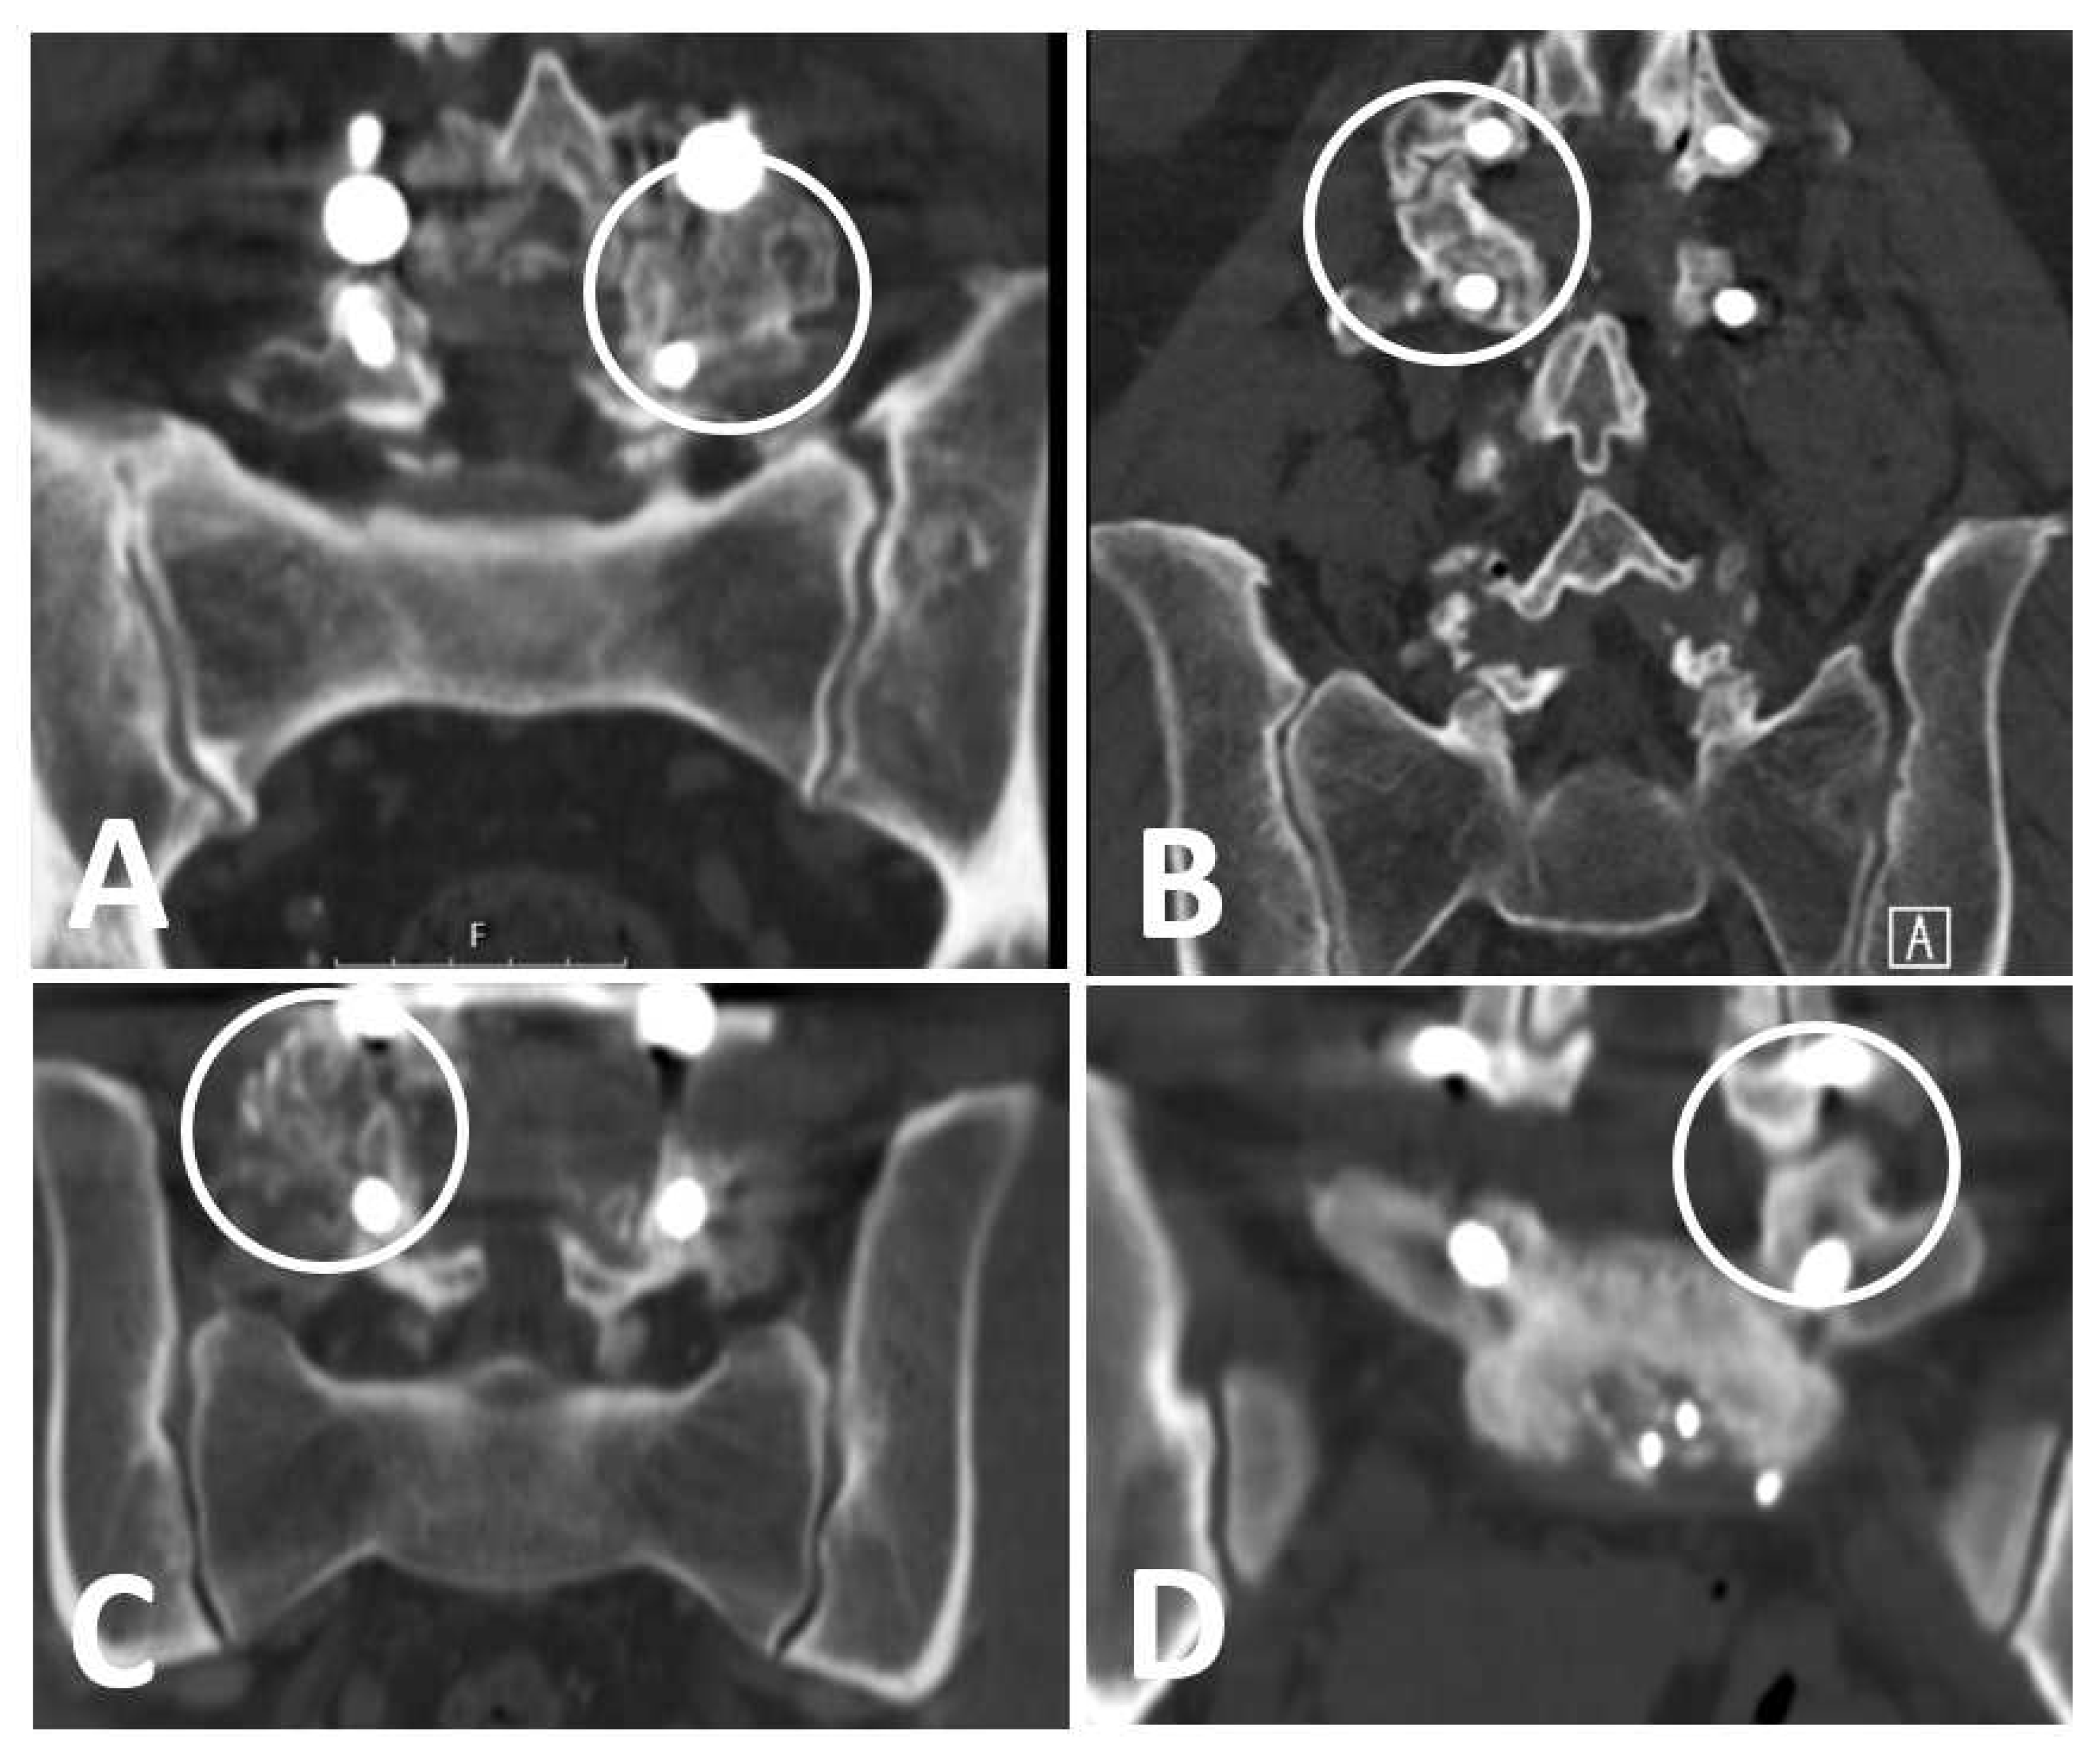

Figure 2.

Examples of Lee’s fusion criteria. (A) Definite fusion, (B) probable fusion, (C) possible arthrosis, (D) definite pseudoarthrosis.

- Definitive fusion: definitive bony trabecular bridging across the graft–host interface.

- Probable fusion: no definitive bony trabecular crossing but with no gap at the graft–host interface.

- Possible arthrosis: no bony trabecular crossing with identifiable gap at the graft–host interface.

- Definite pseudarthrosis: no traversing trabecular bone with definitive gap.